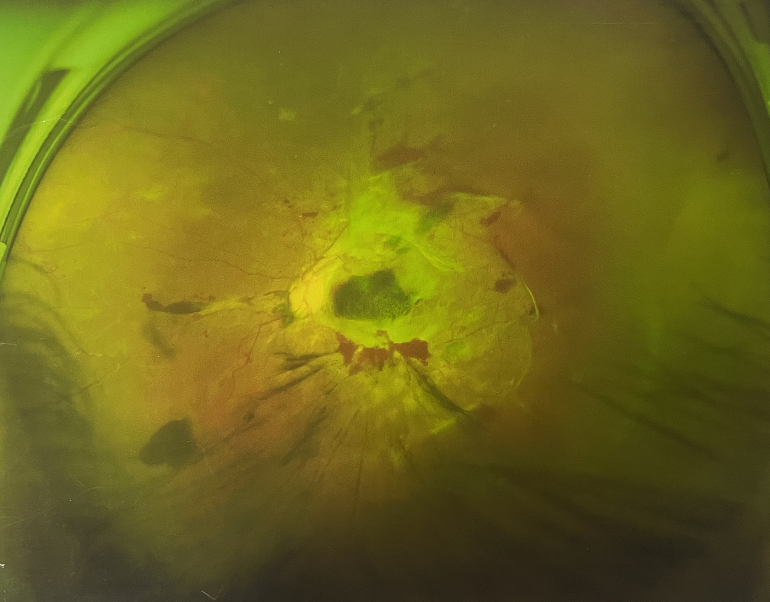

4個(gè)月前的左眼

左眼發(fā)展到糖尿病視網(wǎng)膜病變VI期

由于王女士的左眼沒有聽從醫(yī)生盡快做手術(shù)的建議,一直耽誤,從4月前的0.4視力逐漸下降到僅剩眼前手動(dòng),導(dǎo)致左眼發(fā)展到糖尿病視網(wǎng)膜病變VI期(屬于6期糖網(wǎng)中的晚期),已經(jīng)產(chǎn)生大量新生血管+纖維增值+廣泛牽拉性視網(wǎng)膜脫離,由于耽誤了病情,且病情發(fā)展異常迅速,導(dǎo)致目前左眼連保住眼球都很困難。

“而如果4月余前,左眼及時(shí)手術(shù)(當(dāng)時(shí)左眼病情比右眼輕,增殖膜還未累及黃斑),左眼將恢復(fù)的比右眼還好,甚至可以恢復(fù)到0.8或1.0,而現(xiàn)在連保住眼球的機(jī)會(huì)都很渺茫”,張小虎醫(yī)生表示實(shí)在可惜。